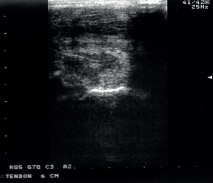

– entre 3 et 10 jours après l’accident

– choix des traitements à réaliser et la convalescence

– donner un pronostic

– aide au suivi et à changer de palier d’activité

– agrandissement naturel de la lésion durant les deux premières semaines

– immobilisation correcte durant les 10 premiers jours permettait de limiter significativement cette augmentation de taille de la lésion (David et al. 2011)